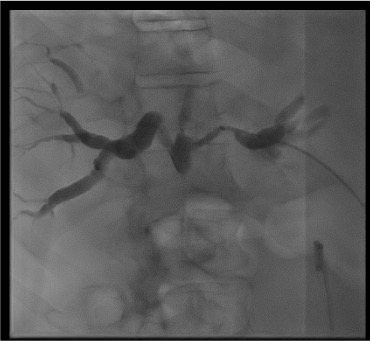

Cholangiogram

Bilateral obstruction — Klatskin tumor

Likely cause: Bismuth III-IV hilar cholangiocarcinoma obstructing both right and left hepatic duct systems independently.

Next step: May need two separate drains (left + right system). Ideally placed same session if patient tolerates; otherwise staged 48 hours apart. Limit to draining the two ducts providing the most functional liver volume. Bismuth IV bilateral drainage rarely achieves meaningful benefit — limit attempts.